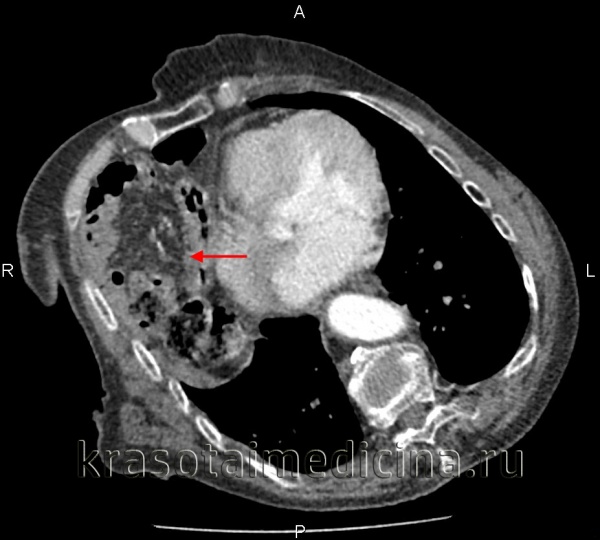

КТ молочной железы. Травматическое событие кишечника, сальника в грудной полости.